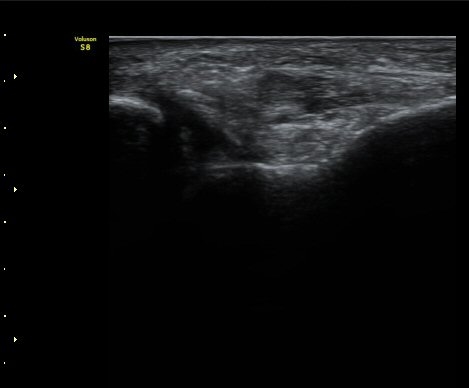

Á¾µ¹ºñ°ñÀδë Á¾´Ü¸é°Ë»ç¿¡¼­ Á¾°ñºñ°ñÀδë´Â Á¤»óÀûÀÎ ¸ð¾çÀ¸·Î °üÂûµÈ´Ù(±×¸² 3, 4).

ÃÊÀ½ÆÄ°Ë»çÇÏ Àü°Å°ñºñ°ñÀÎ´ë ºÎÇϰ˻翡¼­ °Å°ñ°ú ºñ°ñ°£ ºÒ¾ÈÁ¤ÀÌ °üÂûµÈ´Ù(÷ºÎ µ¿¿µ»ó).

Á¤Áö »óÅÂÀÇ Àü°Å°ñºñ°ñÀδë ÃÊÀ½ÆÄ°Ë»ç¿¡¼­´Â ÀδëÀÇ Àú¿¡ÄÚ ºÎÁ¾ÀÌ °üÂûµÇ´Âµ¥

ÀÌ ¼Ò°ßÀ¸·Î´Â ÀÌ ÀδëÀÇ ±â´É ¼Ò½ÇÀ» È®ÀÎÇÒ ¼ö ¾ø´Ù.

±×·¯³ª ÃÊÀ½ÆÄ Åõ½ÃÇÏ ºÎÇϰ˻縦 ½ÃÇàÇÏ¸é °Å°ñ°ú ºñ°ñ»çÀÌÀÇ ¾ÈÁ¤¼ºÀÌ ÈѼյǾî

º¸´Ù Àû±ØÀûÀÎ Ä¡·á°¡ ÇÊ¿äÇÑ °ÍÀ¸·Î ÆÇ´ÜµÈ´Ù.